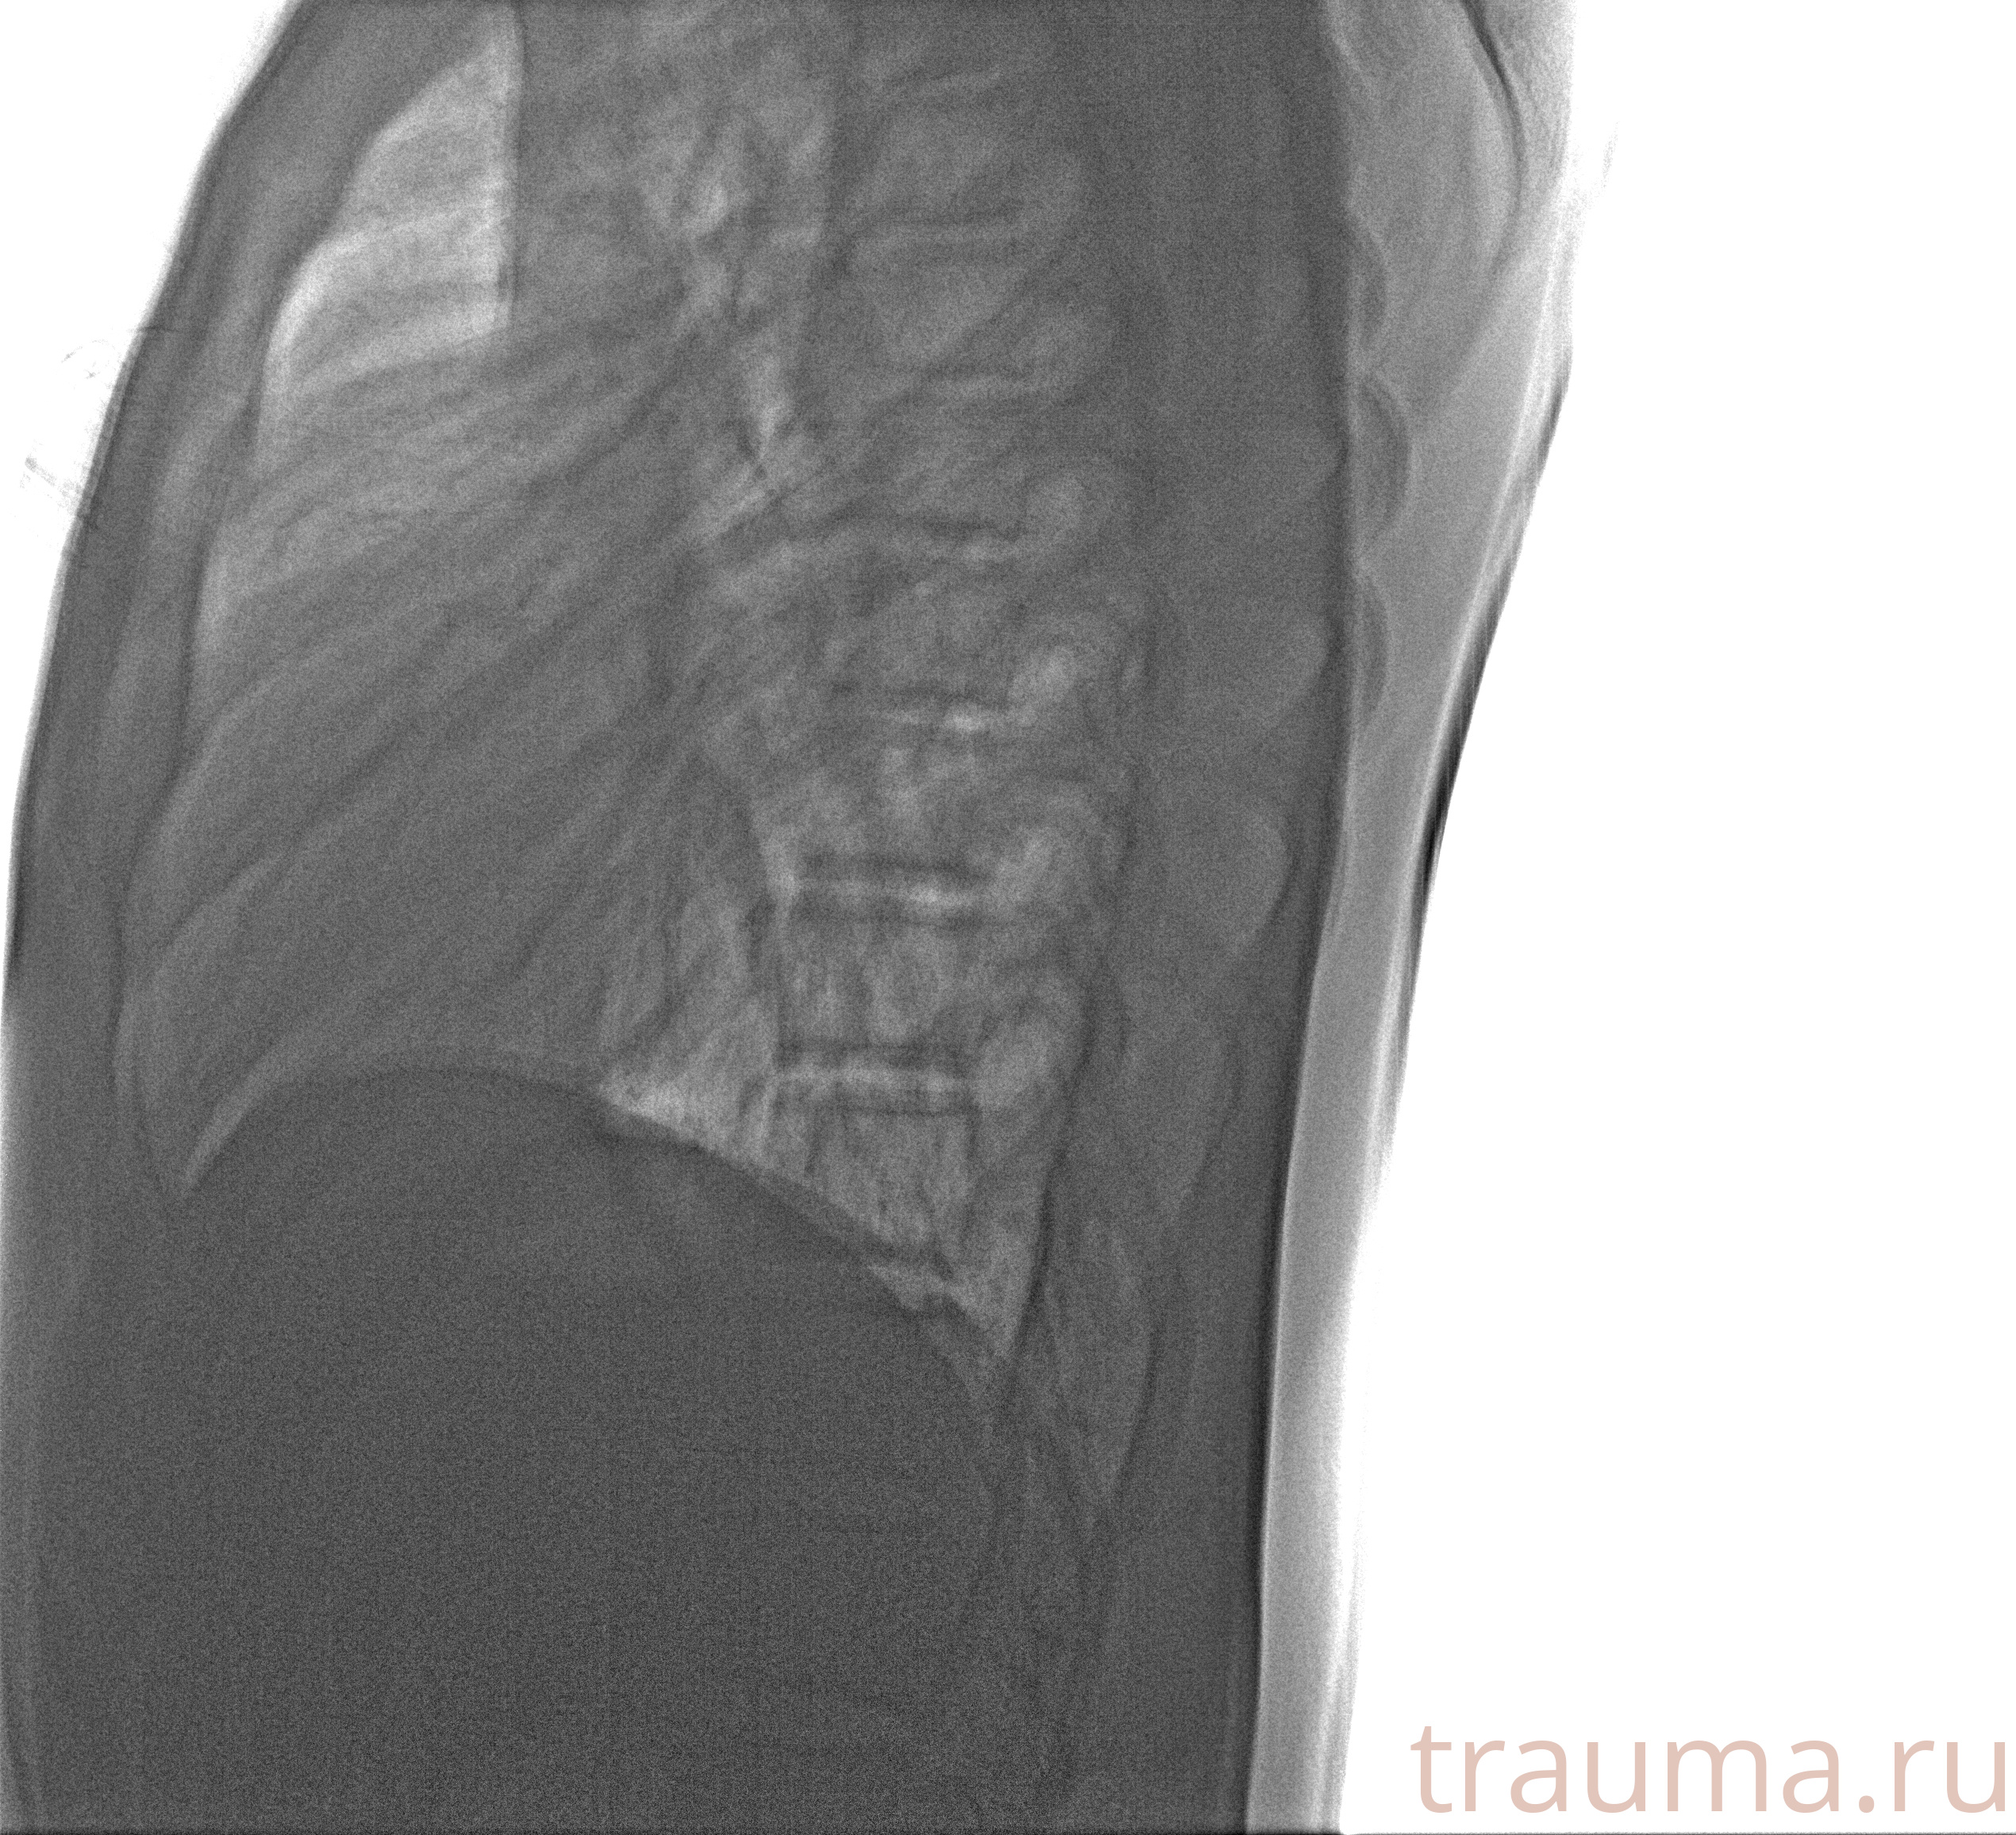

Рентген на дому: по вашему адресу приезжает врач-рентгенолог, травматолог-ортопед с мобильным рентгеновским аппаратом, проводит диагностику травмы или заболевания, делает необходимые рентгенограммы, дает рекомендации по дальнейшему лечению. Получить качественные снимки в домашних условиях возможно благодаря уникальной методике, разработанной МосРентген Центром для института  Склифосовского